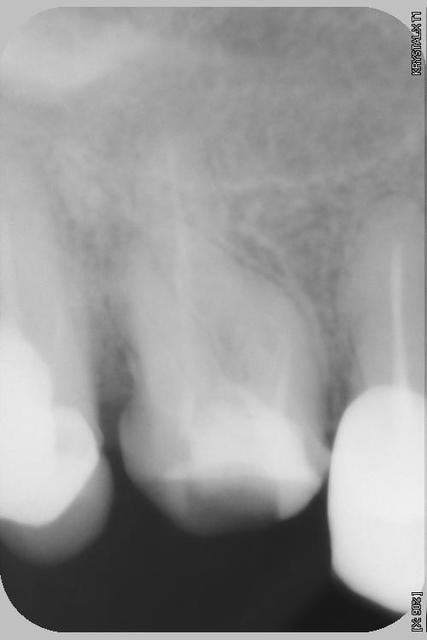

Patiente adressée, douleurs chronique sourde depuis 5 ans au niveau de la 16, ses differents dentistes depuis ne voulaient pas lui demonter la couronne en absence de signes radiologiques.(Ironie du sort je fais parti de ces differents dentistes puisque j'avais moi meme recue cette patiente en urgence en 2007!)

Apres quelques temps sur le fauteuil je suis parvenue a instrumenter le MV, et j'ai deouvert un faux canal sur le palatin, apres quinzes jours le signes cliniques ont disparuent.

Alors origine des douleurs? Pour moi ce n'est pas le MV mais bien le faux canal de la racine palatine, bien que la patiente se soit retrouvée chez moi a cause de la courbure du MV.